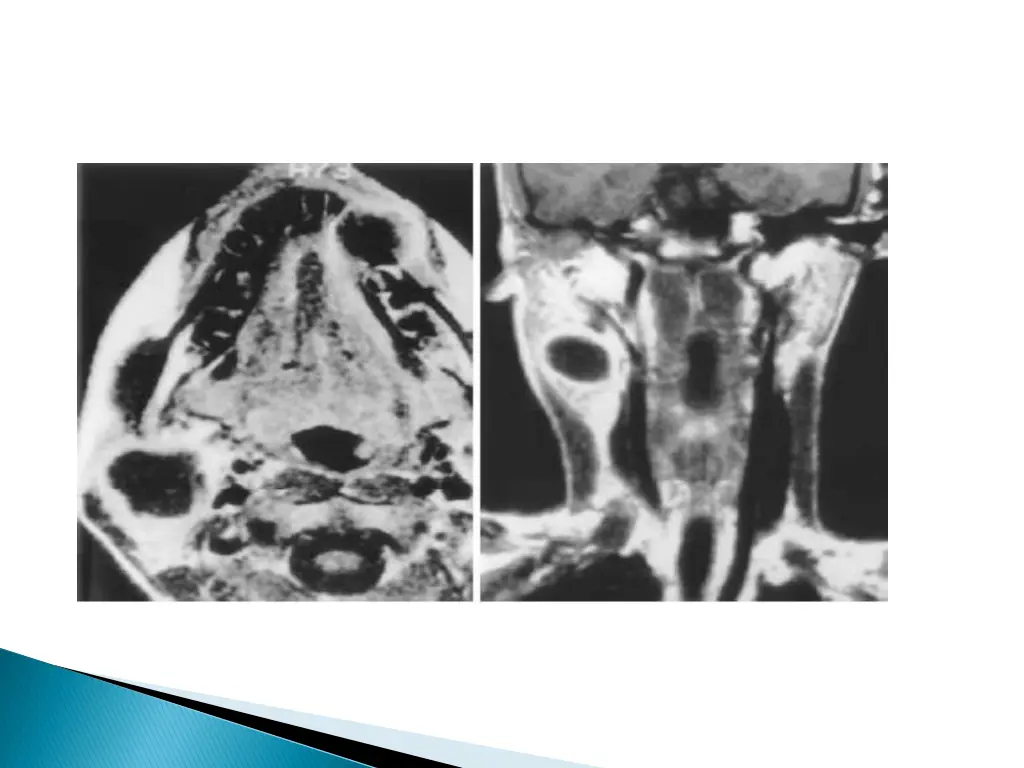

UNCOMPLICATED CYST : hypo on T1W and hyper on T2WI with smooth non enhancing wall. INFECTED/HAEMORRHAGIC CYST: thick irregular wall with enhancement. variable signal intensities depending on the protein content.

MRI better depicts the deep tissue extent. Cyst fluid hypo/hyper on T1W and hyperintense on T2WI. Occasionally, BEAK SIGN : on axial CT/MRI image : pathognomic of a 2ndbranchial cleft cyst especially bailey s type III cyst It represents a curved rim of tissue or a beak pointing medially between the ECA and ICA.